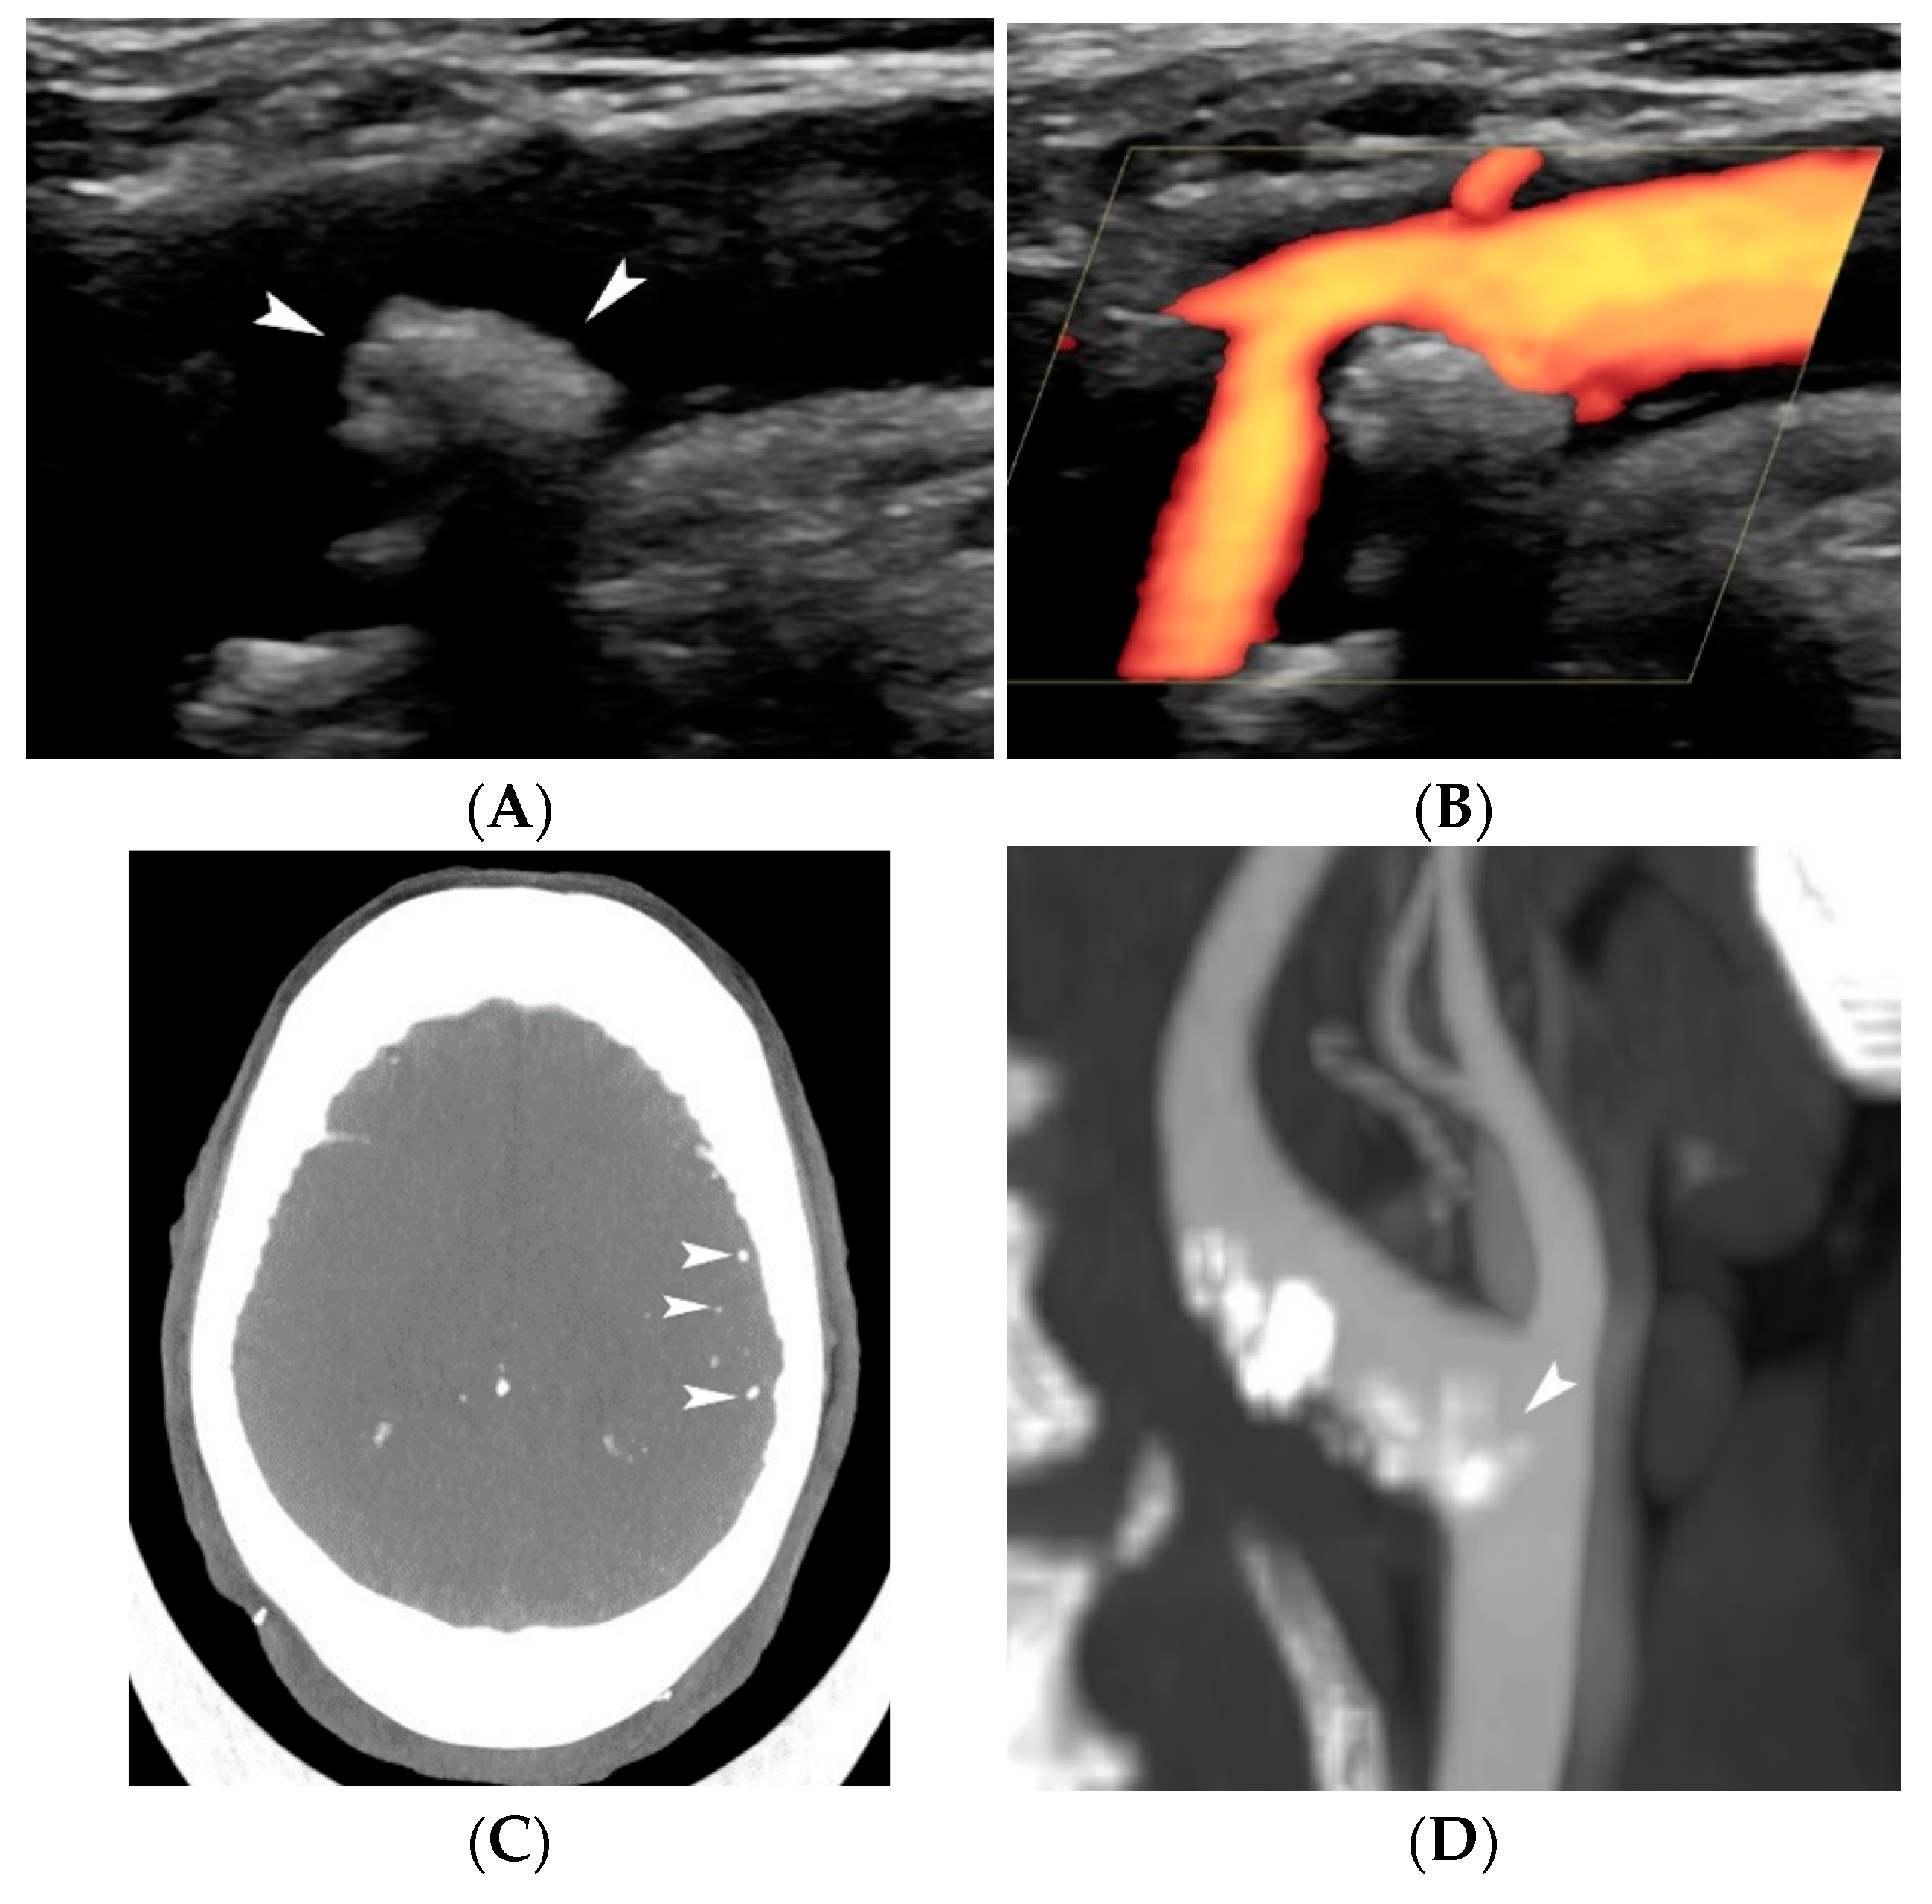

4.1.4. Plaque Ulceration

3. Surface Morphology

4. Contrast-Enhanced Ultrasound (CEUS)